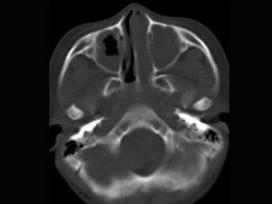

问题 男,7岁,无意发现鼻腔肿物,无明显症状,CT如图所示,最可能诊断为 ( )

选项 A、鼻乳头状瘤 B、鼻炎及副鼻窦粘膜下囊肿 C、鼻炎 D、鼻炎鼻息肉 E、鼻淋巴瘤

答案 D